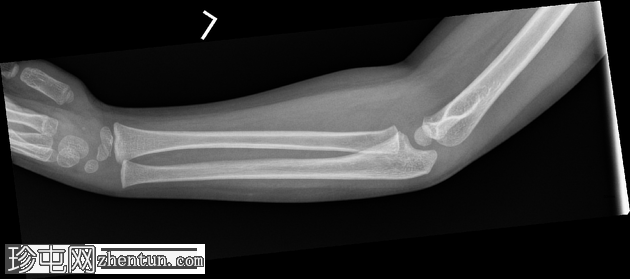

X光片

1.png

正面

在正位片和侧位片上,桡骨近端干骺端可见轻微的皮质断裂和不规则,骨折线似乎向骺端延伸。

相关的脂肪垫征(可见前脂肪垫和帆状征,后脂肪垫阳性)进一步支持骨折后关节内积液的存在。

总体而言,骨性对线保持良好,无脱位迹象。

骨化中心与年龄相符。